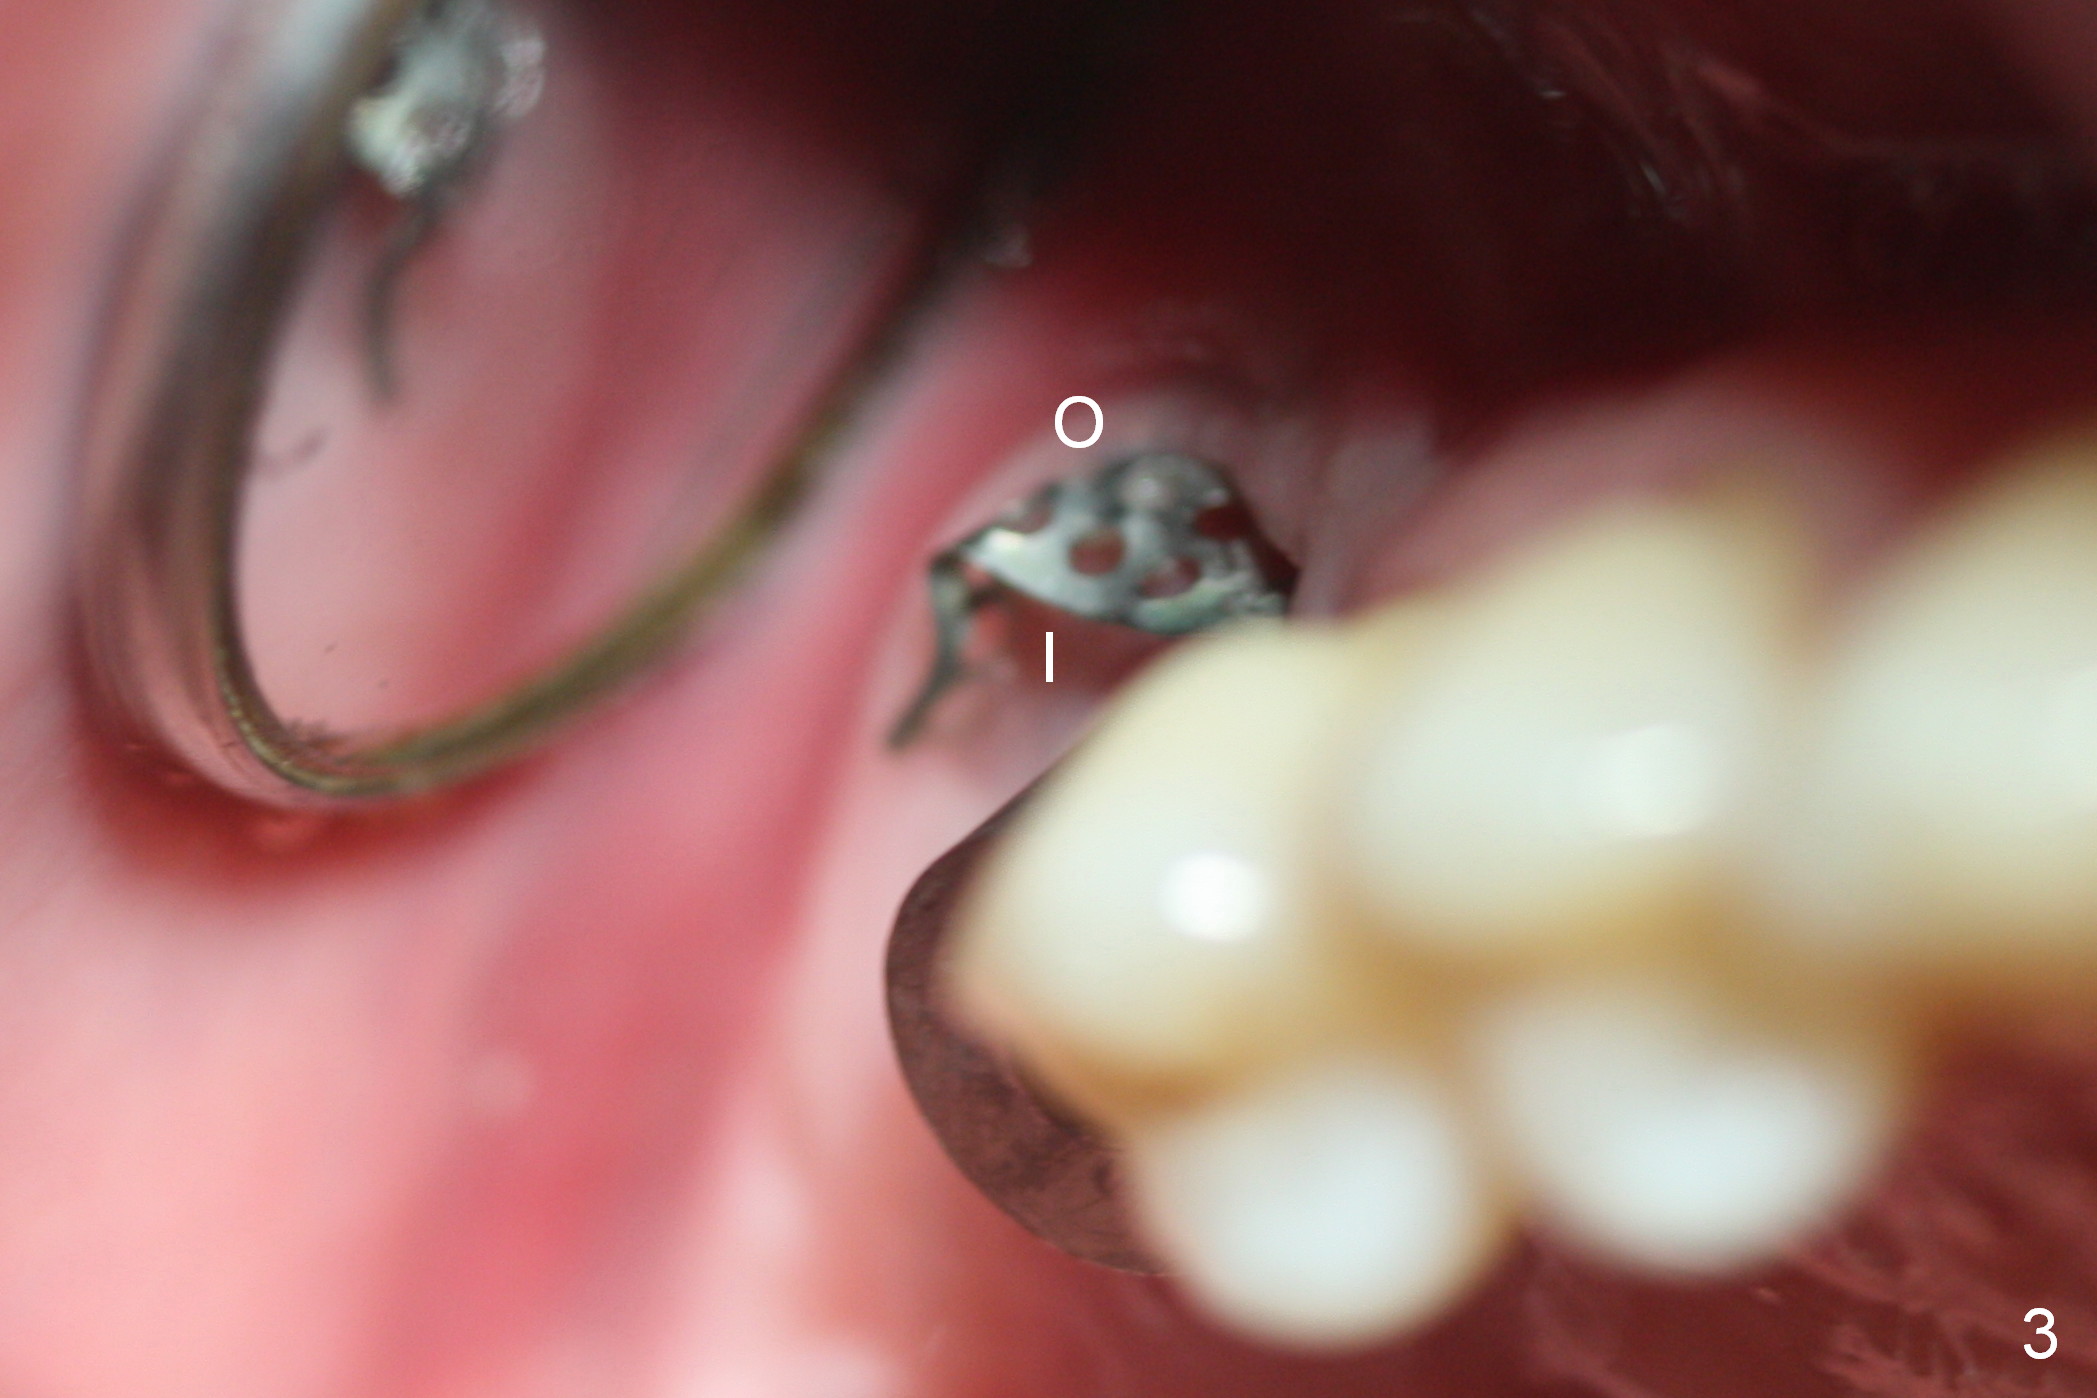

Three months post 2nd bone graft, the gingiva inside the Titanium mesh (used to be granulation tissue 1 month postop (Fig.2)) turns (Fig.3 I) as mature as the outside portion (O). When the mesh is removed, there is no thread exposure. The inner and outer portions of the gingiva are sutured later (Fig.4). The implant is restored immediately. It appears that Titanium mesh exposure is not a severe complication. If asymptomatic, leave the gingiva to heal by itself. Use small size of the mesh and release of soft tissue as much as possible may reduce the chance of mesh exposure.